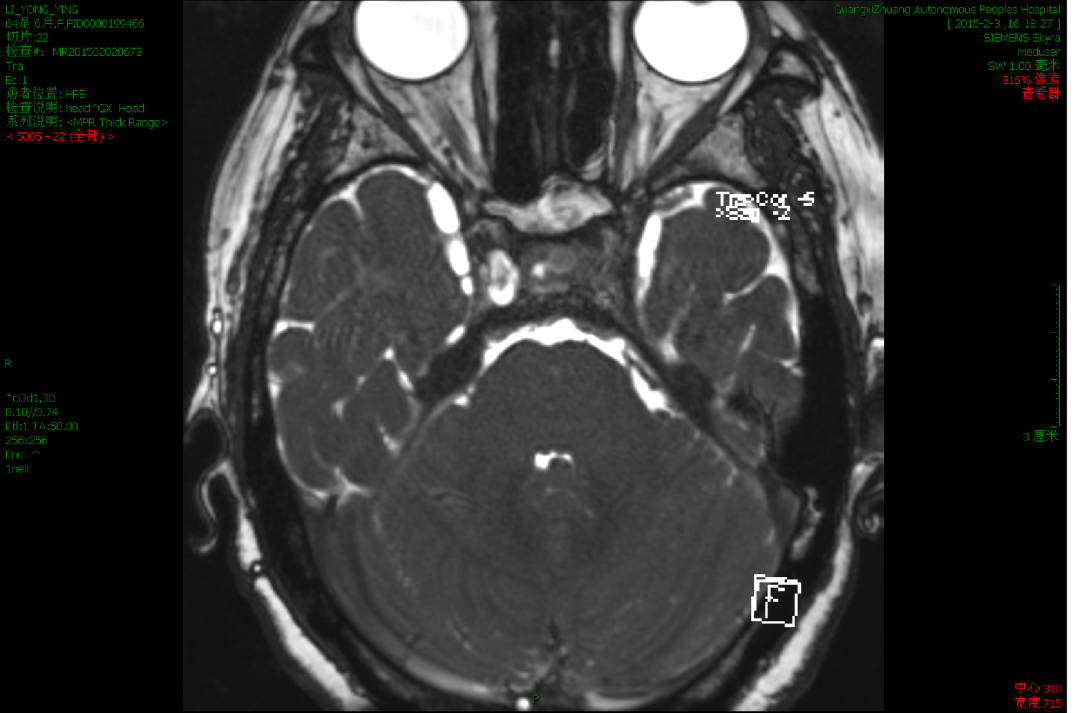

2015-4-1 MRI

2015-4-1